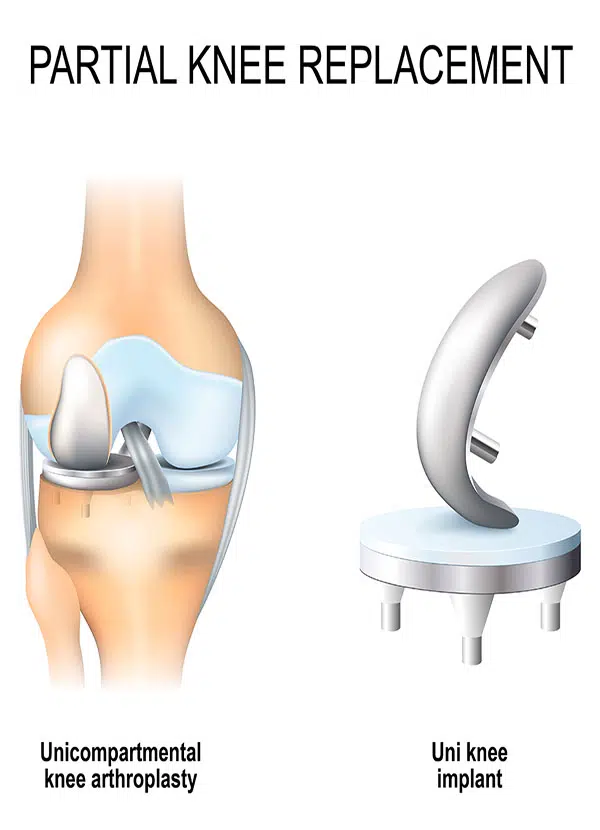

人工膝関節置換術 Total Knee Arthroplasty 全人工膝(ひざ)関節置換術(Total Knee Arthroplasty:TKAの詳細情報

全人工膝(ひざ)関節置換術(Total Knee Arthroplasty:TKA。COPYRIGHT UNION HOSPITAL 手術資料。Total knee replacement surgery (TKA) - Stock Illustration。人工膝関節置換術に関する専門的な内容を網羅した書籍。。关节置换术(膝关节置换)| 伊丽莎白医院。- タイトル: 人工膝関節置換術- サブタイトル: Total Knee Arthroplasty- 出版社: 南江堂- 定価: 1800円ご覧いただきありがとうございます。